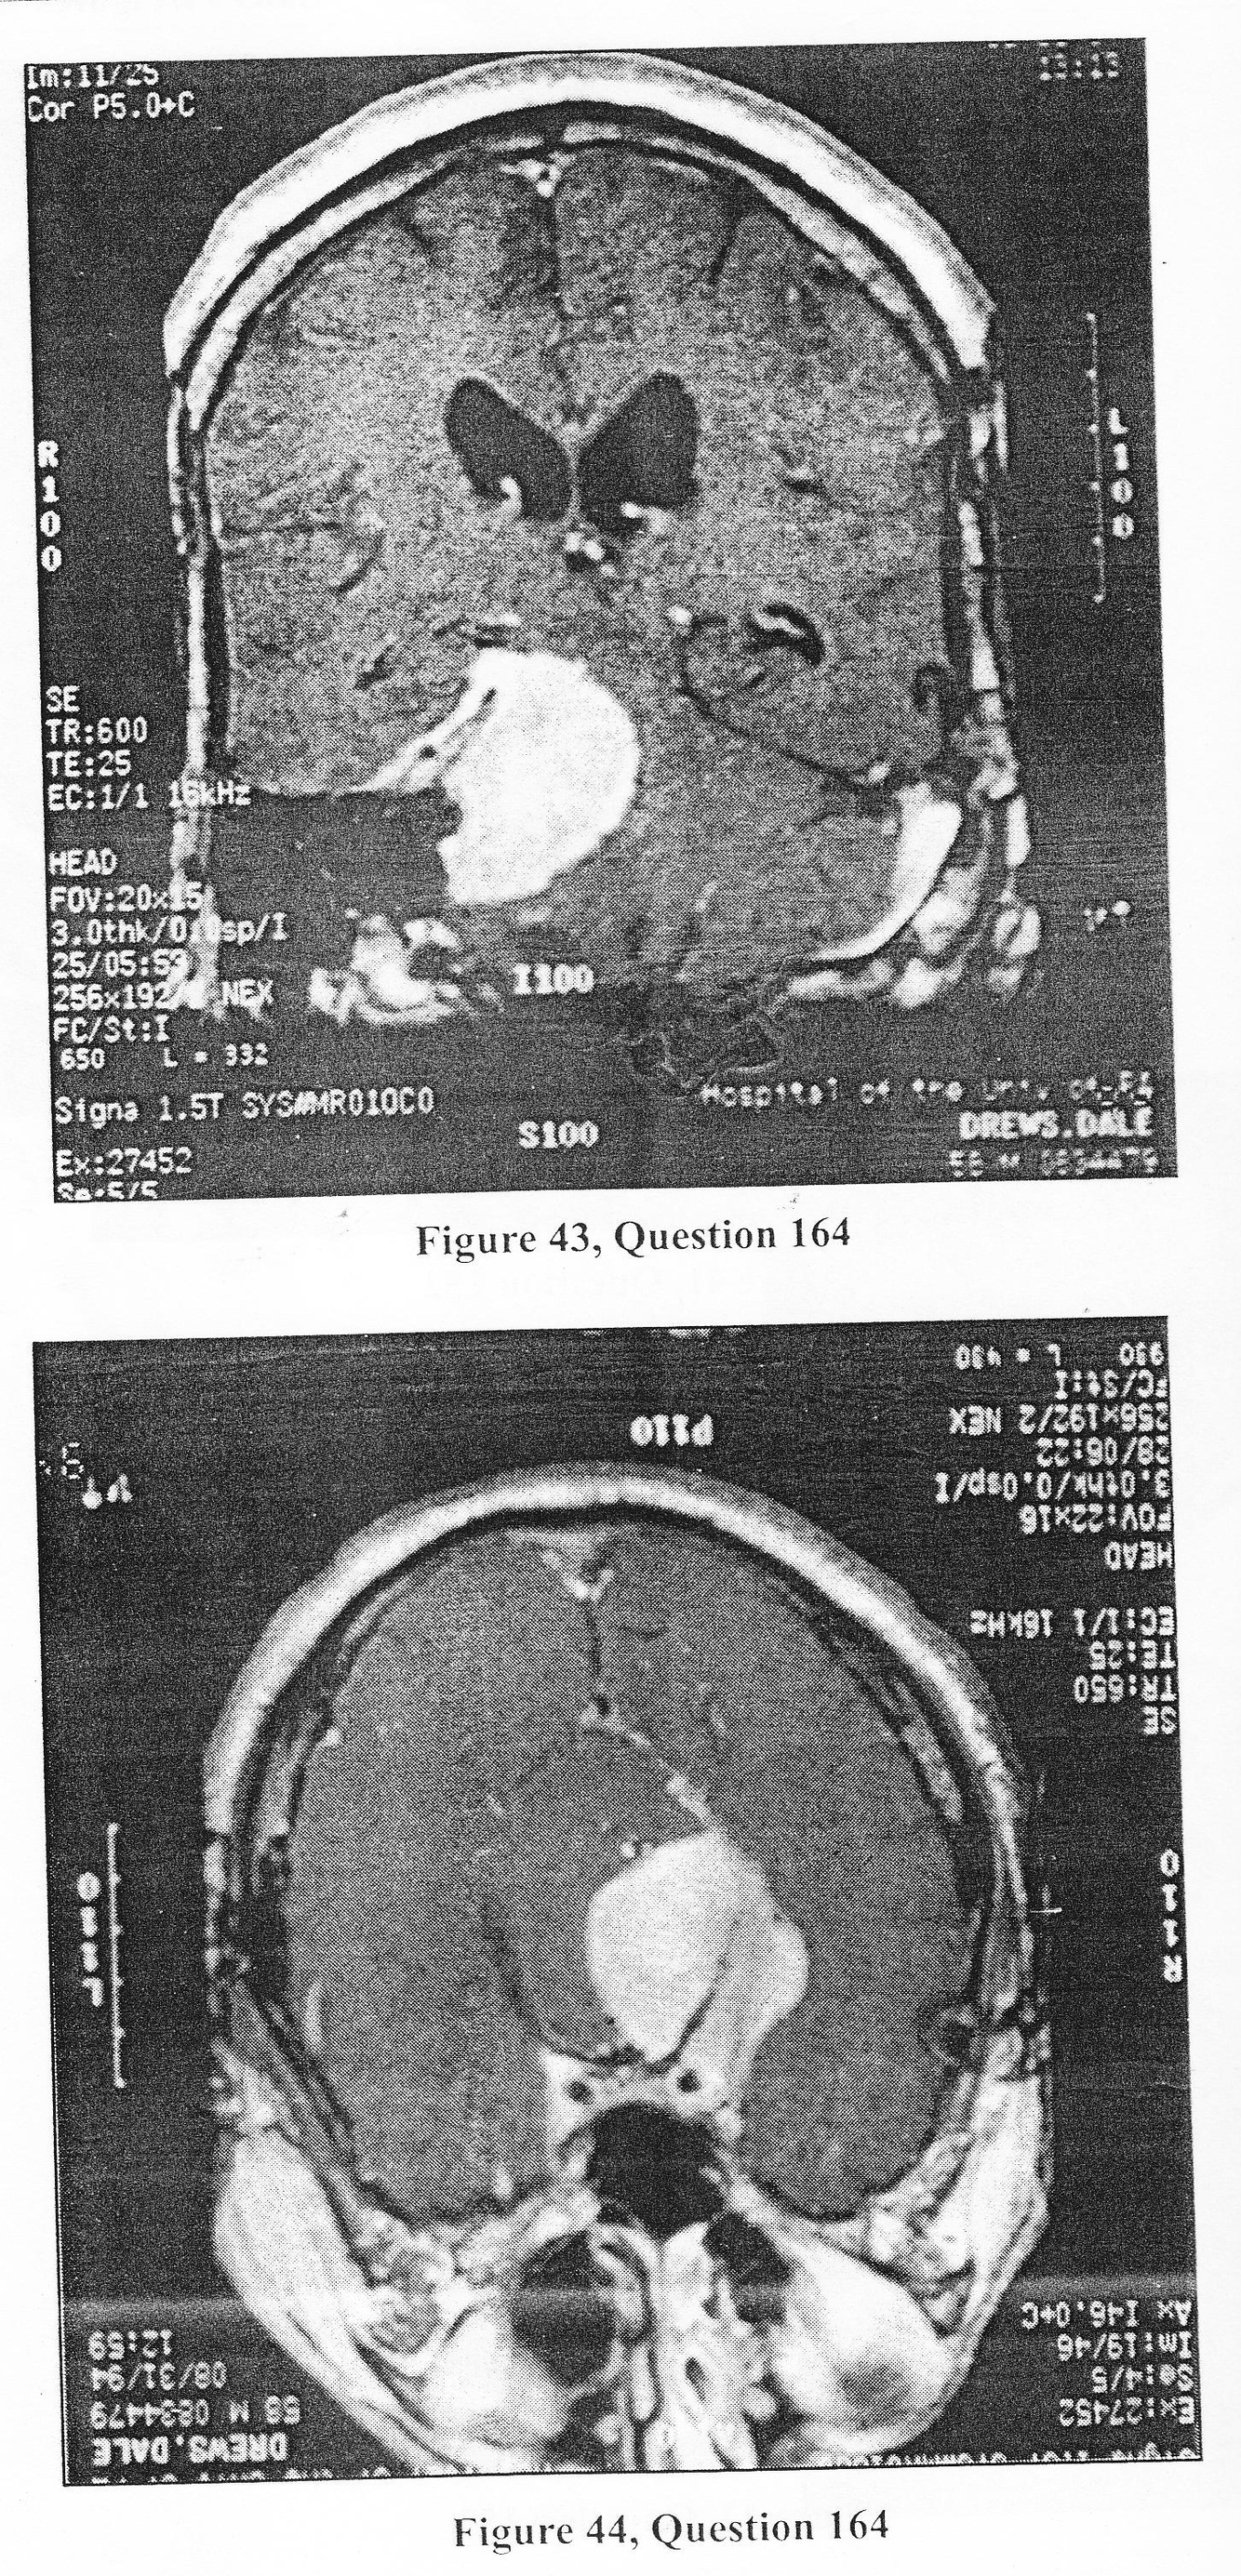

55-year-old man who was otherwise healthy presented with approximately 2-3 months of progressive diplopia, right-sided facial numbness, and ataxia. Neurologic examination was normal, with the exception of a right-sided sixth nerve palsy, decreased corneal reflex on the right, and an extensor Babinski response on the left side. His gait is ataxic. Figures 43 and 44 depict coronal and axial MRI examinations on this patient.

B. petroclival meningioma

D. all of the above

C. petrosal approach (combined supratentorial/subtemporal and infratentorial/presigmoid craniectomy and transtentorial resection of tumor)